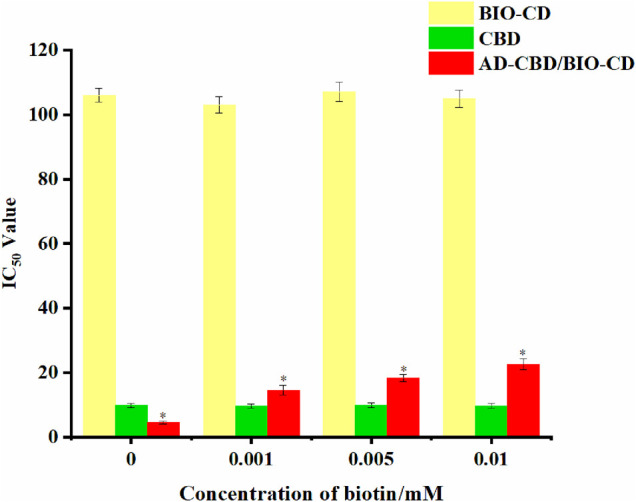

BIO-CD Targeting Verification Experiment

Different concentrations (0.001, 0.005, and 0.010 mM) of biotin were added into culture medium previously to verify the cancer targeting ability of biotin. The cells were cultured at 37°C with 5% CO2 for 24 h to design different levels of biotin to combine with the receptors on the surface of biotin cancer cells. Then new culture medium containing different concentrations of CBD, AD-CBD, BIO-CD, AD-CBD/BIO-CD were added to the cells and continued to cultivate for 48 h. Finally, we used the previous mentioned method to measure the OD value and calculate the IC50 value of CBD, AD-CBD, BIO-CD, and AD-CBD/BIO-CD.

Verification Experiment of Cancer-Targeting of Biotin

In our study, we evaluated the IC50 values of the AD-CBD/BIO-CD inclusion complex on A549 which cultured with multiple concentrations of biotins. The IC50 values without biotin pretreatment were also tested. As shown in Figure 11, the IC50 value of the AD-CBD/BIO-CD inclusion complex gradually increased with the increase of the amount of biotin. It might be attributed to the gradual occupation of biotin receptors on the surface of cancer that resulted in a decrease of targeting ability of the inclusion complex. In addition, without targeting ability, IC50 values were almost unchanged for CBD, AD-CBD, and BIO-CD.